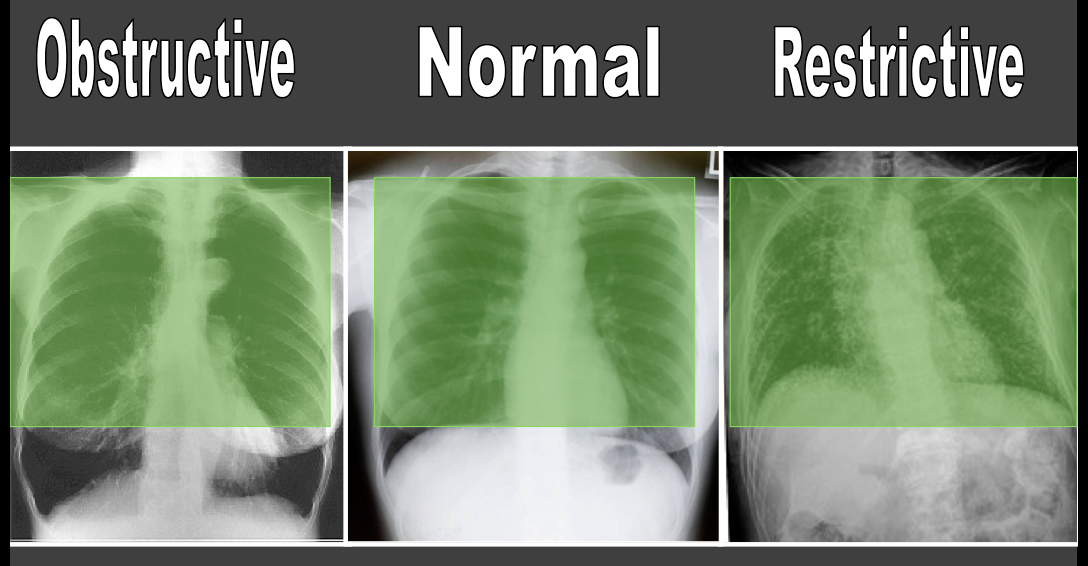

What is the key pulmonary function test that can clue you in that there is a restrictive disorder going on?

TLC (total lung capacity) - this is the main factor reduced so it should be the main thing you look for. increased FEV1/FVC will also likely be seen but is variable (it would be the same as identifying emphysema on the basis of TLC)